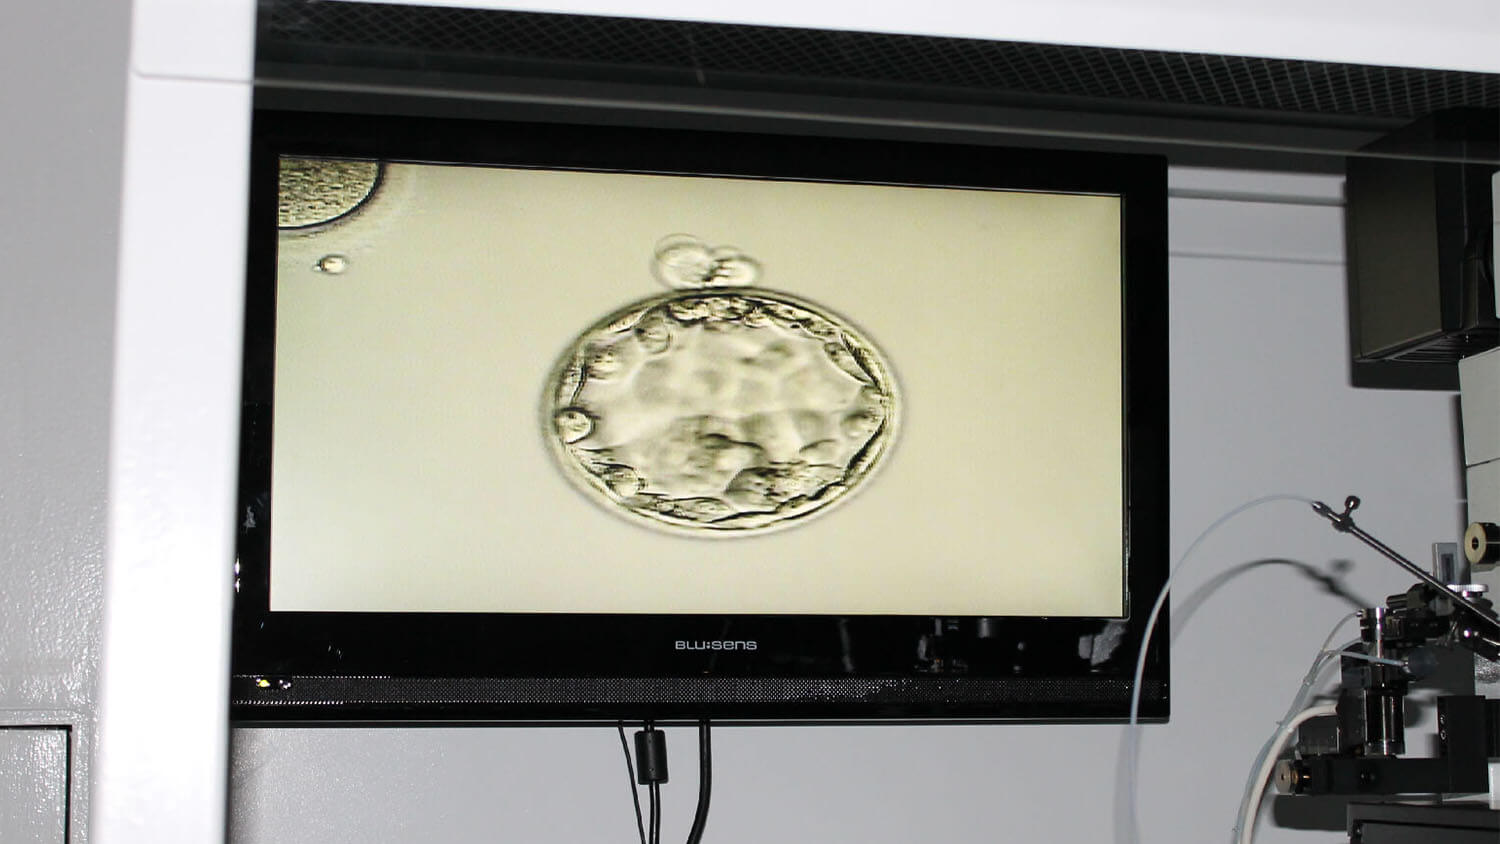

Eclosión Asistida en IREGA.

Morfocinética